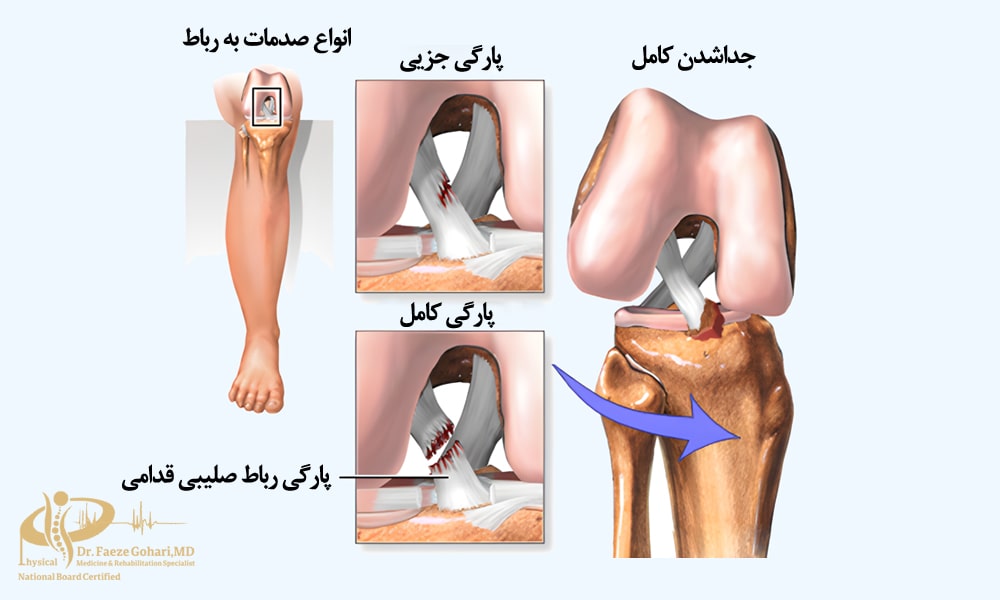

در آسیبهای رباطی (بهویژه رباط صلیبی قدامی (ACL)) مانند پارگی جزئی یا کشیدگی رباطهای زانو، تزریق PRP با رساندن فاکتورهای رشد به ناحیه آسیبدیده، باعث کاهش التهاب، تسریع ترمیم بافت رباط و تقویت استحکام آن در طول زمان میشود. این درمان بهویژه در مواردی که پارگی کامل نیست و بیمار نیاز فوری به جراحی ندارد، میتواند بسیار مؤثر باشد.

حتی در حین جراحی بازسازی رباط نیز استفاده از PRP میتواند مفید باشد؛ مطالعات نشان دادهاند که افزودن PRP در زمان جراحی میتواند روند پذیرش و بلوغ پیوند را تا ۲۰ تا ۳۰ درصد بهبود بخشد. این موضوع به ترمیم بهتر بافت، استحکام بیشتر رباط بازسازیشده و بازگشت سریعتر به فعالیت کمک میکند.